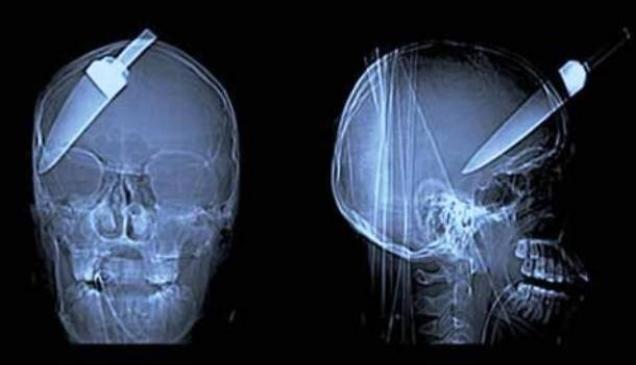

21 WTF x-rays

these are just creepy

Uploaded 7 years ago in Creepy